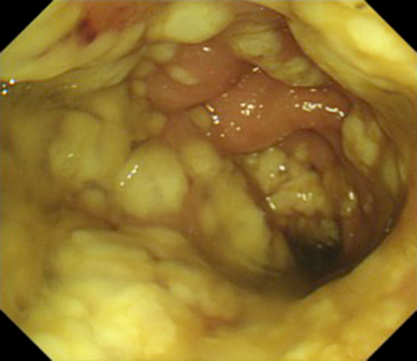

現病歴①:2016年10月,腹痛・下痢精査の下部消化管内視鏡検査(以下,CFSと略記)で全周性の横行結腸癌と診断され自己拡張型金属ステントを留置,上部消化管内視鏡では胃角後壁にIIa+IIc病変を認め胃癌と診断された.2017年1月に手術目的に入院,第4病日に横行結腸切除+幽門側胃切除術を施行した.病理組織所見は大腸癌(T,circ,type 5,40×35 mm,tub2,pT4a,int,INFb,ly0,v2,PN1a,pN0,pPM0(75 mm),pDM0(80 mm),pT4aN0M0,pStage II)および胃癌(M,Post,Type 0-IIc,17×9 mm,tub1,pT1a,ly0,v0,pN0,pPM0(27 mm),pDM0(65 mm),pT1aN0M0,pStage IA)であった.第17病日にドレーン造影で残胃十二指腸吻合の縫合不全を認め(Fig. 1),ドレーン排液の培養よりSerratia marcescensを検出した.第27病日に38.0°Cの発熱を認め,Serratia感染と中心静脈カテーテル感染を念頭にceftriaxone(以下,CTRXと略記)およびVCM点滴を開始した.第36病日に38.2°Cの発熱に加えて腹部膨満,右季肋部痛が出現した.第39病日の血液検査ではWBC 49,620/μl,CRP 19.9 mg/dlの高度炎症反応亢進とBUN 23.6 mg/dl,Cre 1.01 mg/dlの軽度腎機能障害を認め(Table 1),腹部単純レントゲンでは右側結腸の拡張と回腸の一部にもガス貯留を認めた(Fig. 2).腹部超音波検査では胆囊腫大や壁肥厚を認めず,胆囊炎は否定的であった.縫合不全からの敗血症と診断し,CTRXを増量した.炎症反応の改善を認めたためCTRXが有効と判断し,第42病日にVCMを中止したが,第43病日にAST 690 U/l,ALT 471 U/lの肝機能障害が出現した.CTRXによる肝障害を疑い,抗生剤をcefozopranに変更した.その後肝機能障害は徐々に改善し排便は認められたが,37°C台の稽留熱と軽度の腹部膨満は継続した.下痢は認めなかった.第46病日に38~39°Cの弛張熱を認め,腹部骨盤造影CTで全結腸および直腸の壁肥厚像を認め(Fig. 3a~f)腸炎と診断した.第47病日のCFSで直腸からS状結腸にかけてびまん性に偽膜の付着を認め偽膜性腸炎と診断し(Fig. 4),同日の血液検査でAlb 2.1 g/dl,WBC 13,750/μl,臍部に圧痛を認めたが腹膜刺激症状は認めないため,American College of Gastroenterology(以下,ACGと略記)ガイドラインの重症(severe disease)と診断し,VCM 125 mg×4回/日を開始した.

Sigmoidoscope shows diffuse pseudomembrane over mucosa of the sigmoid colon and rectum.